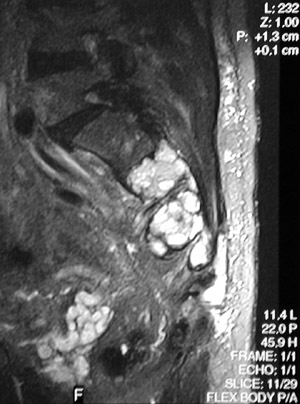

| The pelvic MRI scan view above in axial view demonstrates brightly enhancing osteolytic metastases extending from the sacrum across the sacroiliac joint on the left. In this case, the primary neoplasm was a renal cell carcinoma. The same metastases in sagittal view are seen below. |